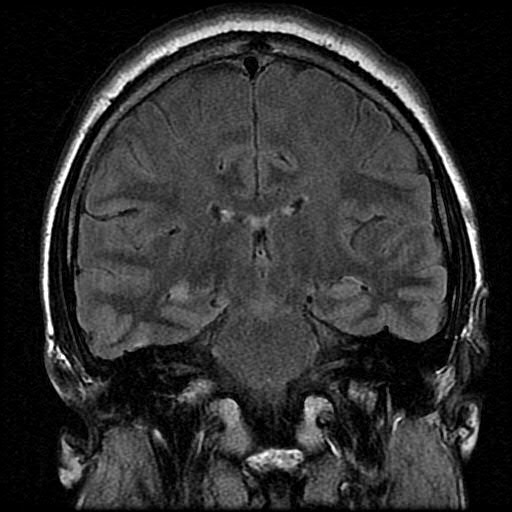

Right Mesial Temporal Sclerosis (MTS) with Flair

Also, see arrow in figure at the top of the page.